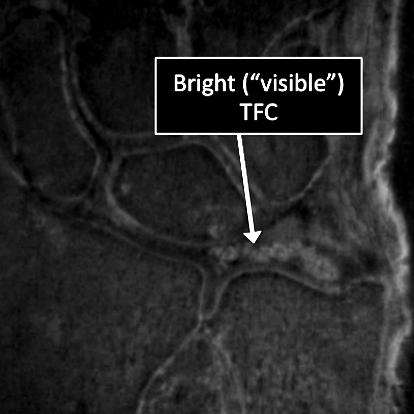

Why Translational MRI of the wrist?

- In the wrist, as in many other parts of the body there are certain structures that can’t be seen (they look black or dark) with the standard MRI.

- There are new “software” programs that allow us to see structures with different contrast (bright versus dark).

- Some of these “invisible” or dark structures are unique to the wrist (Triangular Fibrocartilage or TFC) and others are found in other parts of the body (e.g. cartilage, tendons, ligaments, cortical bone).

Wrist MRI examinations using the standard MRI techniques (top) and translational MRI techniques (bottom).